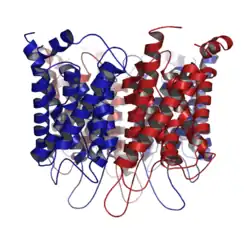

Основным элементом структуры ГЭБ являются эндотелиальные клетки. Особенностью церебральных сосудов является наличие плотных контактов между эндотелиальными клетками. В структуру ГЭБ также входят перици́ты и астроци́ты[23]. Межклеточные промежутки между эндотелиальными клетками, перицитами и астроцитами — нейроглии , меньше, чем промежутки между клетками в других тканях организма. Эти три вида клеток являются структурной основой ГЭБ не только у человека, но и у большинства позвоночных[28][29].

Эндотелий

Капиллярные сосуды выстланы эндотелиальными клетками. Эндотелий сосудов большинства тканей содержит открытые промежутки (фенестра́ции) диаметром около 50 нм и межклеточные щели от 100 до 1000 нм. Через эти промежутки вода и растворённые в ней вещества циркулируют между кровью и межклеточным пространством. Отличительной особенностью сосудов центральной нервной системы является отсутствие как фенестраций, так и межклеточных щелей между эндотелиальными клетками[30]. Таким образом, эндотелиальная выстилка капилляров мозга является сплошной[31].

Другим отличием эндотелия церебральных капилляров от периферических является низкое содержание в них пиноцито́зных пузырьков (вези́кул)[9][32].

Количество митохондрий в эндотелиальных клетках сосудов мозга в 5-10 раз выше, чем в эндотелии периферических сосудов. Столь высокое содержание митохондрий связано со значительными энергетическими потребностями эндотелиальных клеток ГЭБ, осуществляющих активный транспорт и обмен веществ[27]. (Митохондрии — это органеллы, в которых происходит синтез молекул АТФ, являющихся основным источником энергии для клеток.)

ГЭБ является также метаболическим или ферментативным (энзиматическим) барьером[6][33][34][35][36]. На поверхности клеточных мембран эндотелиальных клеток ГЭБ находится целый ряд ферментов, причём в значительно большем количестве, чем на мембранах других клеток паренхимы. Это такие ферменты, как гамма-глутамилтрансфераза и фосфатаза (в частности глюкоза-6-фосфатаза), катехол-О-метилтрансфераза, моноаминоксидаза и цитохром Р450[37][38][39]. Благодаря высокой концентрации ферментов в эндотелиальных клетках ГЭБ многие вещества метаболизируются при транспортировании через цитоплазму этих клеток[9]. Высота (размер в направлении, перпендикулярном стенке сосуда) эндотелиальной клетки ГЭБ составляет от 3 до 5 мкм (для сравнения, высота энтероцитов, эпителиальных клеток кишечника, - 17-30 мкм)[40]

Соотношение холестерина к фосфолипидам в эндотелиальных клетках ГЭБ такое же, как и в эндотелиальных клетках периферических сосудов, и составляет ≈ 0,7[41]. Пассивный транспорт через клеточные мембраны ГЭБ происходит так же, как и пассивная диффузия в других эндотелиальных клетках[42]. В мембранах эндотелиальных клеток содержится большое количество каналов, проницаемых для молекул воды. Они допускают диффузию воды между мозгом и кровеносной системой[43].

Благодаря отсутствию фенестраций и небольшому числу пиноцитарных везикул эндотелиальная выстилка капилляров мозга становится механическим барьером для крупных молекул и инородных веществ. Кроме этого, ГЭБ обладает значительным электрическим сопротивлением — около 1500—2000 Ом. (для сравнения, электрическое сопротивление для стенок капилляров мышечной ткани составляет лишь 30 Ом.)[44]

Плотные контакты

Эндотелиальные клетки сосудов мозга плотно прилегают друг к другу. Между их стенками образуются так называемые плотные контакты, роль которых в обеспечении ГЭБ состоит в том, что они предотвращают проникновение в ткань мозга различных нежелательных веществ из кровеносного русла[45][46]. Плотные контакты между эндотелиальными клетками блокируют межклеточный (парацеллюля́рный) пассивный транспорт[47][48][49]. При этом блокируется парацеллюлярный транспорт веществ как из кровеносного русла в ткань мозга, так и в обратном направлении — из мозга в кровь[29].

Большое количество трансмембранных белков, таких как окклюди́н, разнообразные клауди́ны и замыкательные адгезионные молекулы связывают латеральные отделы клеточных стенок между собой, участвуют в формировании плотных контактов и делают возможным межклеточный транспорт и обмен веществ[50]. Основными белками, обеспечивающими адгезию эндотелиальных клеток и формирование плотных контактов, являются клаудин-5 и клаудин-12[51]. Нокаут гена CLDN5, ответственного за синтез белка клаудина-5, приводил у экспериментальных мышей к тому, что их ГЭБ становился проницаемым для молекул с молярной массой до 800 г/моль. Такие генетически изменённые животные умирали через несколько часов после рождения[52].